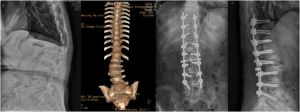

脊柱疾患的臨床與研究

脊柱畸形的影像表現第二節 脊柱外傷的影像表現一 脊髓損傷的診治第一節